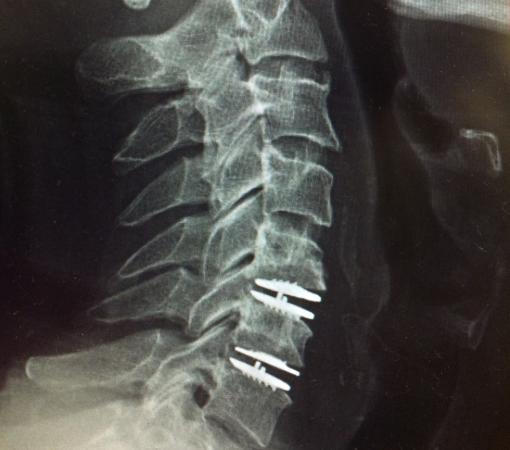

Disc replacement surgery is a procedure designed to alleviate pain caused by damaged or degenerated discs in the spine. The procedure involves replacing the problematic disc with an artificial one, helping to restore normal function and mobility.

For patients experiencing chronic back pain, this surgery can offer relief and prevent the need for fusion surgery.

It’s ideal for individuals who have a herniated disc or degenerative disc disease, providing a more natural range of motion compared to traditional fusion.